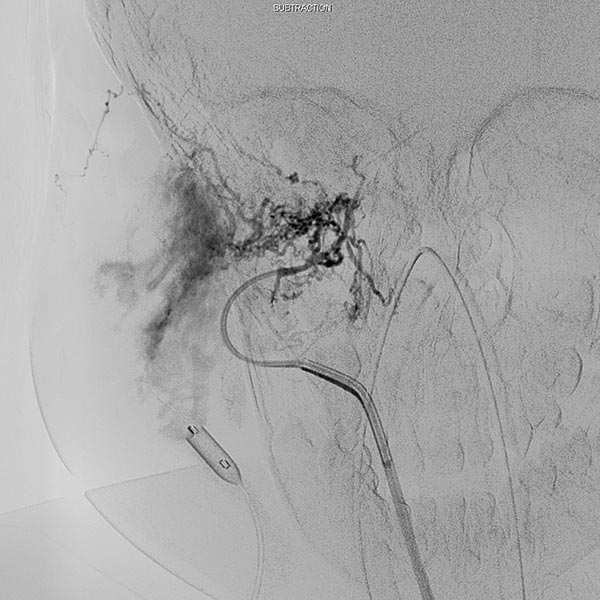

In der digitalen Subtraktionsangiographie (DSA) nach Injektion in die rechte Arteria carotis communis zeigt sich das Hämangiom wie erwartet vor allem aus der Arteria carotis externa versorgt.

Digitale Subtraktionsangiographie (DSA): Nach Einbringen transarteriell eines Führungskatheters 4F in die Arteria carotis externa und Vorbringen eines Mikrokatheters in die Arteria maxillaris. Das Hämangiom zeigt sich als typisches KM-Pooling (Tumorblush). Gut zu sehen auch der transvenös eingebrachte Ballon, der den venösen Abstrom ausblockt. Hier wird jetzt mit Partikeln der Größe 150 Mikron embolisiert ohne dass diese Partikel venös abströmen können.